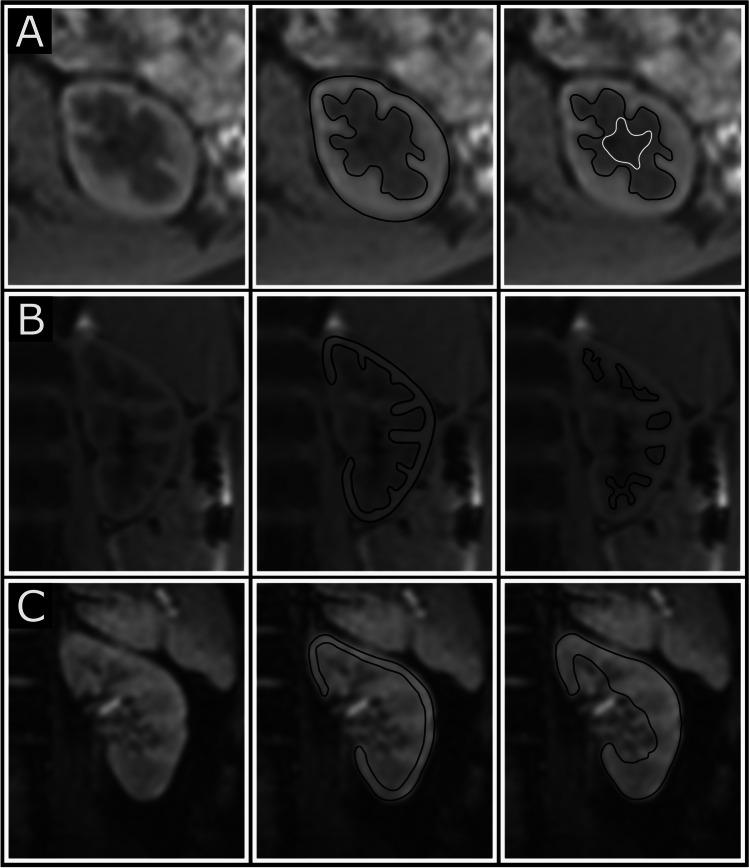

Adolescents born very preterm with FGR and two groups with appropriate birthweight (AGA) were included; one matched for gestational week at birth and one born at term. Cortical and medullary kidney volumes and T1 and T2* mapping values were assessed by magnetic resonance imaging. Biochemical markers of kidney function and renin-angiotensin-aldosterone system (RAAS) activation were analyzed.

FGR with abnormal fetal blood flow followed by very preterm birth is associated with smaller total kidney and medullary kidney volumes, but not with markers of kidney dysfunction or RAAS activation in adolescence. Decreased total kidney and medullary volumes may still precede a long-term decrease in kidney function, and potentially be used as a prognostic marker. A higher resolution version of the Graphical abstract is available as Supplementary information.